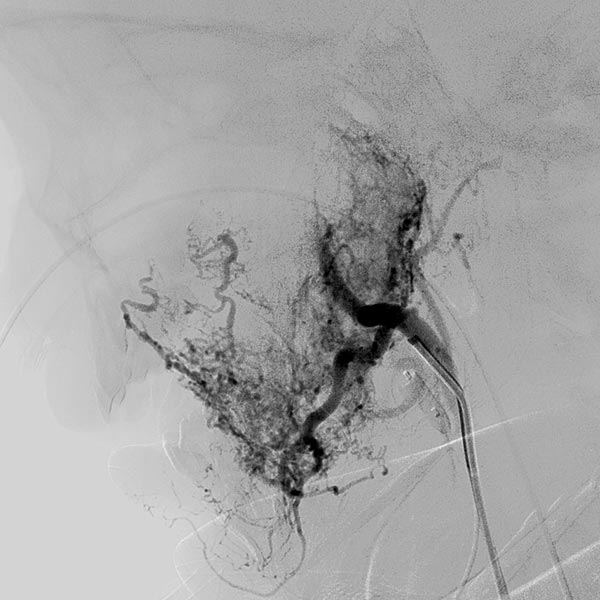

Digital subtraction angiography (DSA) after further super-selective injections with particles via a microcatheter while blocking the venous outflow. A good 50% of the infantile hemangioma has now been successfully occluded.

Digital subtraction angiography (DSA) after super-selective catheterization of the remaining arterial feeder supplying the infantile hemangioma.

During super-selective particle embolization (150 micron particles) via the arterial microcatheter after blocking out the venous outflow, the particles can be seen as a faintly contrasted area.

In the transarterial control angiography via the 4F diagnostic catheter, the infantile hemangioma is not perfused anymore. The typical DSA image of a “defoliated tree” is now shown.

Overview angiography via the common carotid artery after removal of the venous blocking balloon displays a virtually completely devascularized infantile hemangioma. The intracerebral circulation is normal.